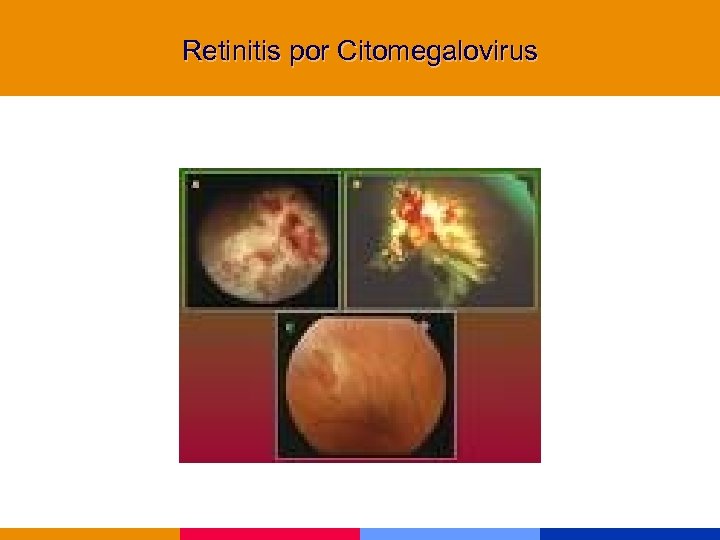

Infecciones por CMV § Afectan a pacientes severamente inmunocomprometidos § Afección de la retina, tubo digestivo, SNC y pulmón § Diagnóstico de retinitis: oftalmólogo entrenado

Infecciones por CMV § Afectan a pacientes severamente inmunocomprometidos § Afección de la retina, tubo digestivo, SNC y pulmón § Diagnóstico de retinitis: oftalmólogo entrenado

Retinitis por Citomegalovirus

Retinitis por Citomegalovirus

Retinitis por Citomegalovirus

Retinitis por Citomegalovirus

Retinitis por Citomegalovirus

Retinitis por Citomegalovirus

Retinitis por Citomegalovirus

Retinitis por Citomegalovirus